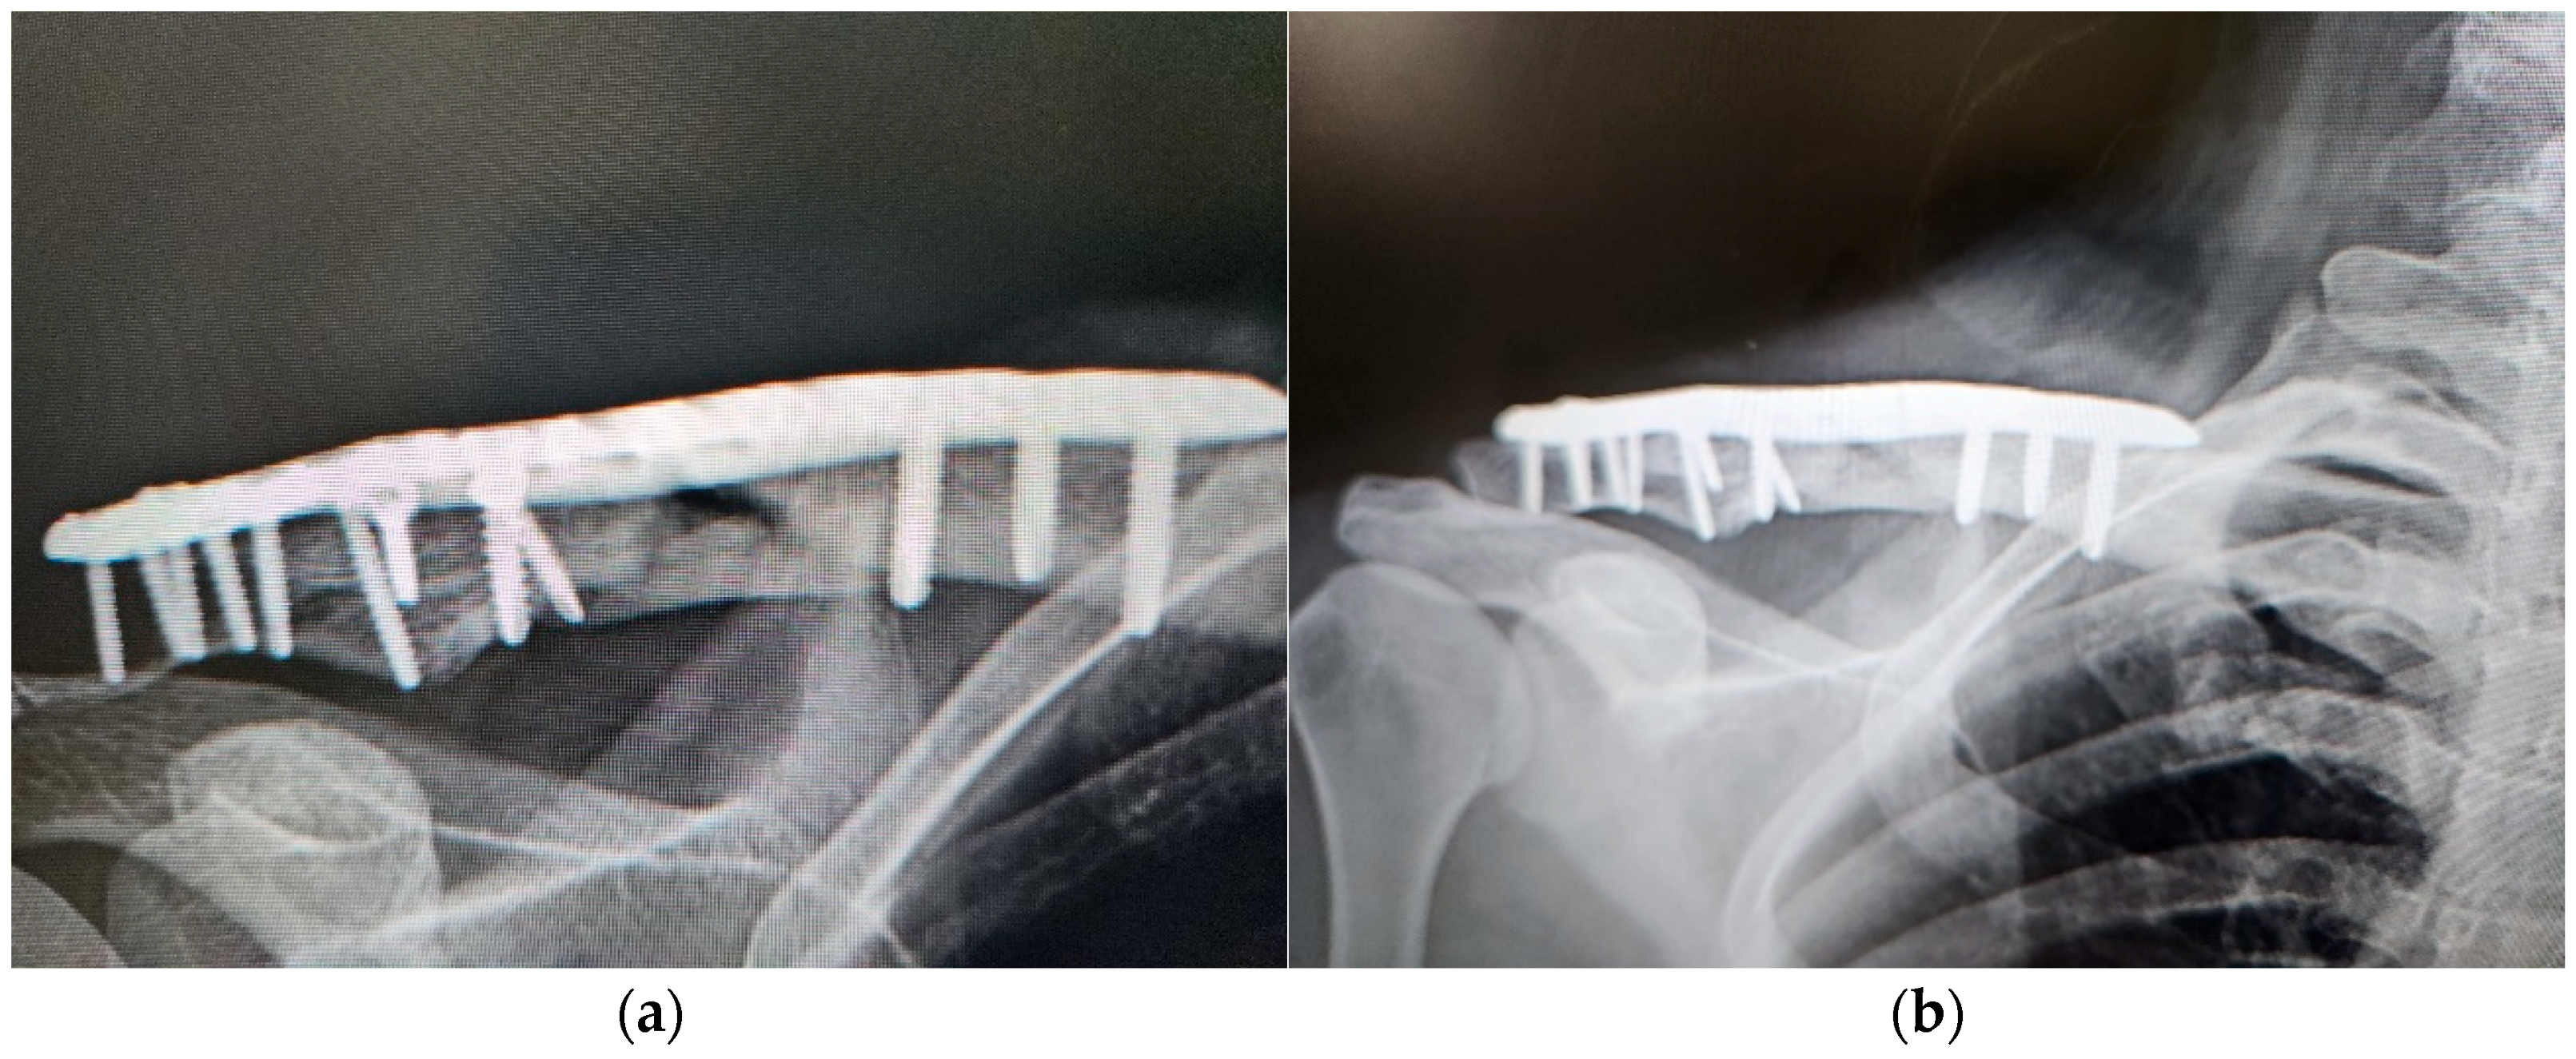

| 4 | 39 | Female | Right clavicle fracture | Non-union after ORIF | Bone defect | 9 | 2 | C-arm fluoroscopy | Intramedullary | 3 | 12 | Union |